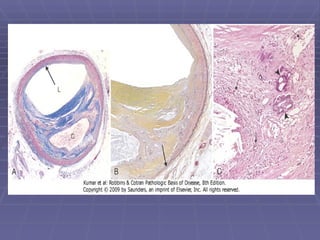

-:ATHEROSCLEROTIC PLAQUE:- Intimal thickening and lipid accumulation. Lodged in the lumen of the artery (0.3-1.5 cm in dia). Grossly they appear as white to yellow patches. Lesions are mostly eccentric but rarely circumferential. Local flow disturbances –increased susceptibility to plaque  formation.

-:DESCRIPTION – PLAQUE:- Typically composed of superficial composed fibrous cap  (smooth muscle cells and collagen). Beneath it contains cellular area.  Deeply containing lipid core, cell debris, foam cells, fibrin, thrombus, plasma proteins. Periphery shows neovascularisation.

-:NATURE OF THE PLAQUE:- Progressively enlarges due to:-  Cell death and degeneration. Synthesis and remodeling of collagen. Organization of thrombus. Often undergo calcification.